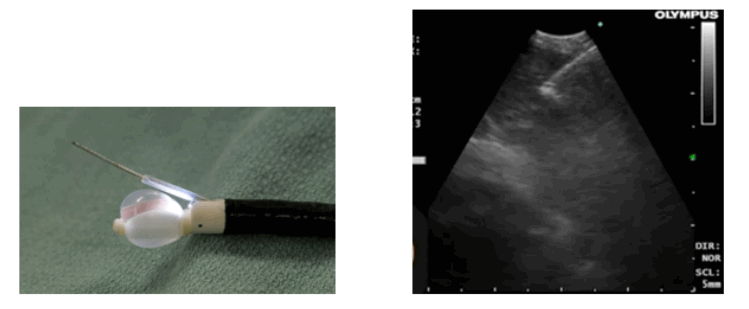

El EBUS consiste en un videobroncoscopio flexible con un diámetro exterior del tubo de inserción es de 6,7 mm, longitud de trabajo 550 mm (longitud total 870 mm). El rango de angulación del extremo distal del endoscopio es de 160° hacia arriba y 90° hacia abajo. El instrumento tiene un pequeño transductor electrónico curvo de matriz lineal, de 10 mm de longitud, ubicado en el extremo distal del endoscopio frente a una lente de fibra óptica de visión frontal oblicua de 30° (ángulo de visión de 80°). El diámetro del extremo distal del endoscopio con el transductor es de 6,9 mm y el endoscopio tiene un canal de biopsia de 2 mm. La frecuencia ultrasónica es de 7,5 MHz con una profundidad de penetración de 5 cm. El endoscopio se conecta a un procesador de ultrasonidos Olympus (US) (EU-C 60). cuyas señales son visualizadas junto con las imágenes broncoscópicas.

A través del canal de trabajo del equipo se introduce una aguja especialmente diseñada, eco refringente, que permite observar ecográficamente en tiempo real su introducción dentro del ganglio o lesión a estudiar.